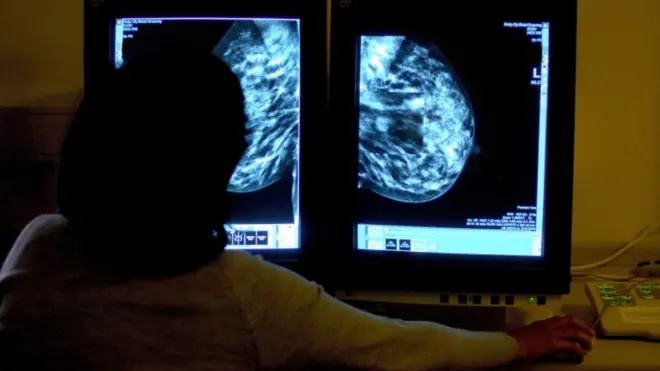

ويعد سرطان الثدي في الوقت الحالي أكثر أنواع السرطان شيوعًا بين النساء في الهند، حيث يمثل 27 بالمئة من جميع حالات السرطان بين النساء.

ويلاحظ أطباء الأورام ارتفاعًا حادًا في عدد حالات الإصابة خلال السنوات الست الماضية.

صدر الصورة، AFP